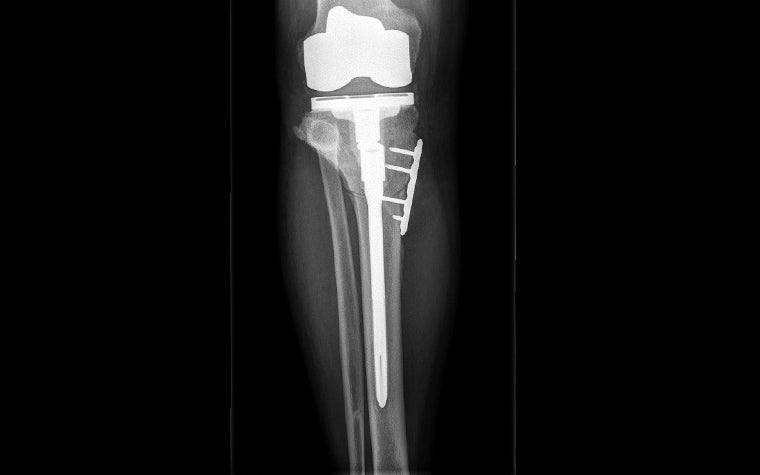

A revision system, the Smith & Nephew Legion, was chosen since the optional offset stem would be used to help with fixation of the tibial osteotomy. Since the OrthoView digital orthopaedic template for the Smith & Nephew Legion behaves as a complete interconnected system, mimicking the behavior of the actual implant, templating for the necessary stem offset is possible.

The resulting preoperative plan provided not only the sizing of the components but also the positioning of the intra-articular cuts and insights into how these would subsequently affect ligament balancing.

- Surgery: The trials for the knee replacement were fitted first, and the knee joint was determined to be a good functional fit — ligament balance with the cuts required being a major consideration.

The osteotomy was followed by disruption of the fibula to perform the inverted dome osteotomy and the use of the revision stem to anchor the bone, along with a small plate for added support. Bony union was anticipated to be adequate due to the nature of the dome osteotomy.

- Outcomes: At his six-week return assessment, the patient was pleased with the progress and results, and he was preparing for the left lower limb to also be repaired to improve function via a similar method.

The union is progressing well with subsequent follow-up, and the patient remains very happy with the outcome.